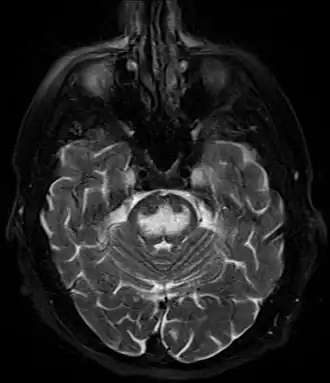

- Магнитно-резонансная томография (МРТ)

Чаще изменения локализуются в нижней части моста имеют вид трезубца или бабочки. Но могут быть также в базальных ганглиях, среднем мозге и белом веществе субкортикальных областей. Накопление контрастного вещества возможно.

Ранние изменения (в первые 24 часа от развития тетрапареза): гиперинтенсивный сигнал (что говорит об ограничении диффузии) в режиме DWI. Изменения в режимах Т1- (гипоинтенсивный сигнал) и Т2-ВИ (гиперинтенсивный) могут развиваться не сразу (до 2 недель). Другие последовательности: FLAIR: гиперинтенсивный, ADC: низкий сигнал